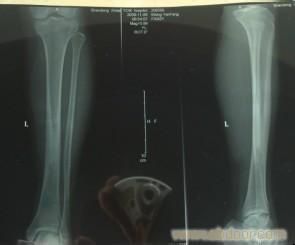

作品目錄輕微。只有在急性血源性骨髓炎,全身症狀嚴重。前軀症狀有全身倦怠,繼以全身...、活動障礙。血源性骨髓炎早期有局部劇烈疼痛和跳痛,肌肉有保護性痙攣,肢體...。如果跖腱受到長期、持續、過大的牽拉,即可在跟骨結節的附著處發生慢性損傷...